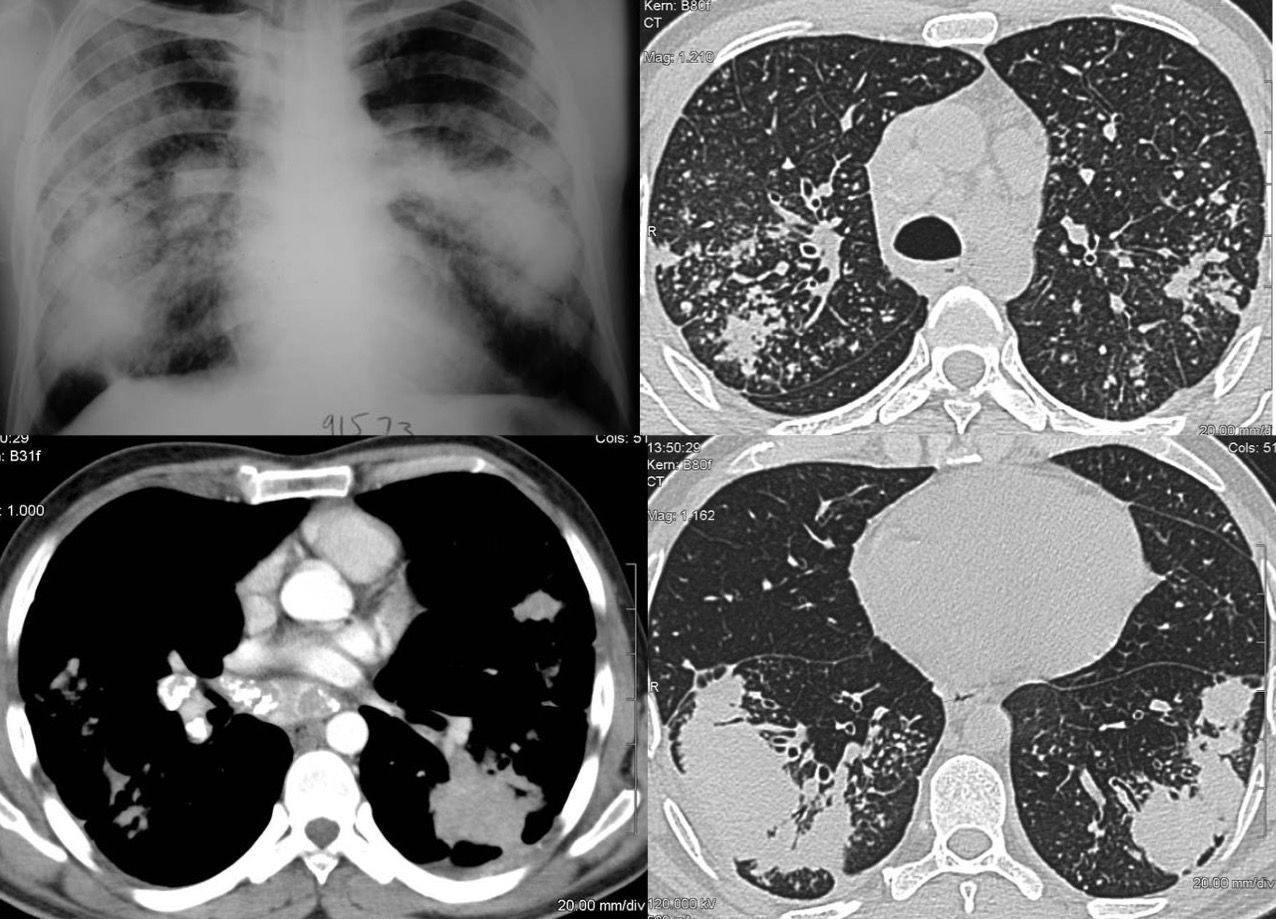

Case 14: Covid-19 Angiopathy with Perfusion Defects at 3 Weeks Paid Members Public

3 1/2 weeks after a diagnosis of Covid-19, the lungs show extensive perfusion defects without pulmonary thrombosis